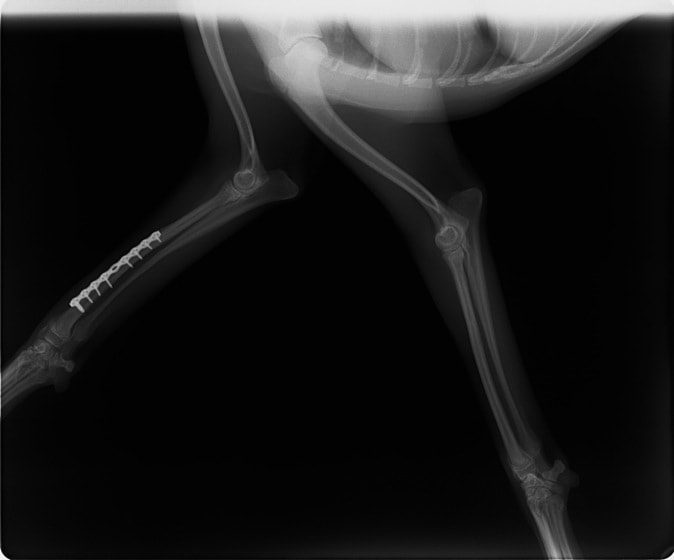

トイプードル 右遠位橈尺骨短斜骨折のALPSによる内固定

橈尺骨骨折 : 症例1 | 症例2 | 症例3 | 症例4 | 症例5 | 症例6 | 症例7

当院ではAdvanced Locking plate system(ALPS)と、Locking compression plate system(LCPS)という骨接合法で骨折症例の治療を行っています。

従来型のプレートのように広い面積で骨と接するプレートを用いて固定を行った場合、プレート下の骨はプレートとの接触面において血行が絶たれ壊死し、それがリモデリングされると骨密度が低下する。この骨密度の低下防ぐために、骨折部局所への血行を温存することの重要性が近年改めて認識されるようになってきている。Advaed Locking Plate System (ALPS)は従来型のプレートシステムの欠点を改良し、より使いやすく、より骨への血行を阻害しないようにというコンセプトで作られた。

- ロッキングスクリューと圧着型スクリュー(皮質骨スクリュー)の双方が使用できる